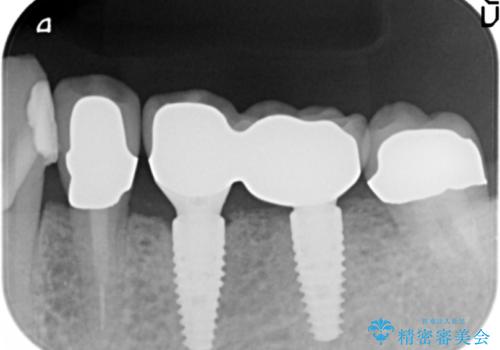

[歯周ポケット除去] 歯周病を改善してからの前歯部ブリッジ

- 前歯のブリッジの再作製を希望されて来院されました。

そのまま外して作製するのではなく、歯周病の問題を解決し(歯周外科)歯と歯ぐきの問題を解決した後に精度の高いブリッジを作製していきます。

セラミック治療前の歯周病治療について

老朽化したかぶせ物による審美障害を改善するために、セラミックによる再治療が必要となることがあります。

この際セラミックの審美性・精度が求められるのはもちろんですが、クラウンを支える歯の状態をきちんと整えておくことが非常に重要です。

具体的には、根管の問題(根管治療の必要性の有無)、歯ぐき・歯槽骨の問題(歯周病の有無)を解決し長い予後が期待できるような状態にしてからの治療が必要です。

今回は前歯のブリッジ再作製の予定部位に歯周病の問題が見られたため、歯周外科手術を行い歯周ポケットを除去した後に歯ぐきの安定を待ち(6ヶ月)最終的なかぶせ物の製作を行いました(メタルボンドブリッジ)。